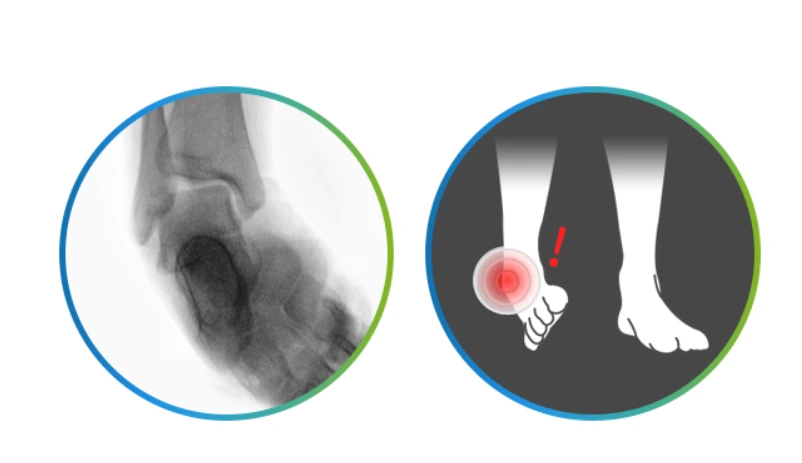

발목이 불안정화되어 있으면 발목 인대나 힘줄의 기능이 떨어지고 발목 염좌 등 질환으로 이어지면 퇴행성 질환까지 유발할 수 있어 각별한 주의가 필요하답니다. 걷기만 해도 통증이 느껴지거나 주로 발목 바깥쪽으로 꺾이는 경우, 발목을 돌릴 때 소리가 나고 뻐근한 통증이 있는 경우, 발에 힘이 실리지 않고 힘이 풀려 주저앉는 경우에는 발목불안정증을 의심해볼 수 있는데요.

발목불안정증.PNG

발목을 접질린 뒤 인대 및 주변 근육 손상에 대한 관리가 제대로 이루어지지 못해 생기는 발목불안정증은 오래 방치하면 인공관절 수술이 필요한 상황으로 악화될 수도 있습니다. 게다가 발목이 불안전하면 자신도 모르는 새 발목이 꺾이면서 넘어져 허리 골절이나 대퇴부 골절 등 큰 사고로 이어질 수도 있어 평소 발목의 안정성을 높이는 운동들을 꾸준히 해주는 것이 좋습니다.